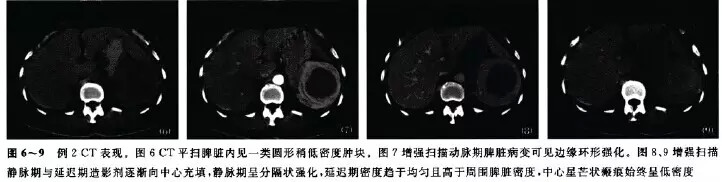

例2 、女,51岁。体检发现脾占位3年,体格检查及实验室检查无明显异常。CT平扫脾内见大小约7.5 cm×6.2 cm稍低密度肿块,边界较清楚;增强后动脉期肿块周边环形强化,静脉期呈分隔状强化,延迟期密度趋于均匀且高于周围脾脏密度,中央瘢痕始终呈低密度(图6~9)。